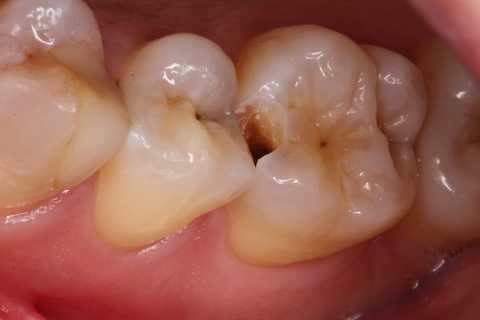

20代女性、右上6、咬合性外傷による隣接面カリエス

この歯は開ける前にエアーでしみていたのだが、開けるとしみなくなった。なんでですかね?

霧吹きの原理でエアスリットが狭い方が象牙細管内のリンパ液が吸い上げられやすいんでしょうね?

クラックが気になるのだが、象牙質には広がっていないようだったので、このまま充填した。

隣の5番はエアブローでしみなかったので、そのままだ。

鏡像、クラック部分は拡大した。